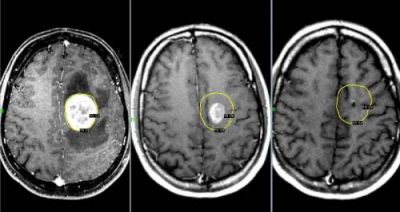

При онкологическом заболевании мозга, у человека далеко не всегда болит голова. Но если такой симптом даёт о себе знать, болезнь протекает очень тяжело.

Головная боль, спровоцированная опухолью мозга, возникает по причине повышения внутричерепного давления. Чем быстрее растёт опухоль, тем сильнее повышается давление.

Возникает такой дискомфорт, преимущественно, утром. Практически всегда он сопровождается рвотой.

По мере прогрессирования заболевания, частота болевых приступов увеличивается, а дискомфорт становится сильнее.

Это приводит к тому, что больной быстро теряет вес, у него появляются судороги. При наличии симптомов рака мозга, следует незамедлительно обратиться к онкологу.

Если вовремя диагностировать заболевание, у больного есть все шансы на выздоровление. Однако если рак будет диагностирован на поздней стадии, шансы на успешное удаление злокачественной опухоли очень малы.

Опухоли мозга

Злокачественные опухоли характеризуются быстрым прорастанием в другие ткани с их последующей трансформацией. При этом метастазы могут наблюдаться сразу в нескольких участках мозга.

Такие опухоли плохо лечатся, а на поздних стадиях их развития спасти человека практически невозможно.

Характер болевых ощущений — постоянный, по мере развития заболевания продолжительность приступов увеличивается. Когда человек двигается, болевые ощущения усиливаются. Сначала они локализуются в области опухоли, потом, по мере увеличения внутричерепного давления, переходят в лобную и затылочную часть. Наиболее сильный дискомфорт наблюдается в ночное и утреннее время из-за скопления жидкости. Вены не справляются с оттоком крови, поэтому к болям прибавляются отёчность и застои. Боли давящие, распирающие, пульсирующие.

К головным болям затем добавляется рвота. При физической нагрузке или кашле болевые ощущения усиливаются, появляется двоение в глазах, временами исчезает зрение. Голова кружится, у пациента нарушается координация движений. Могут неметь конечности, ослабляется тонус мышц.

Иногда бывают эпилептические припадки, путается сознание.

Для диагностики используется МРТ мозга, ПЭТ, КТ мозга, ангиография и другие методы.